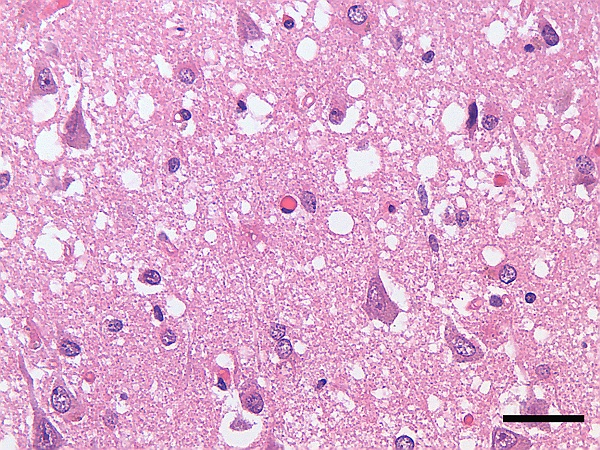

- морфологическое и гистологическое исследование тканей головного мозга (коры, подкорковых ядер) при аутопсии (посмертная диагностика).